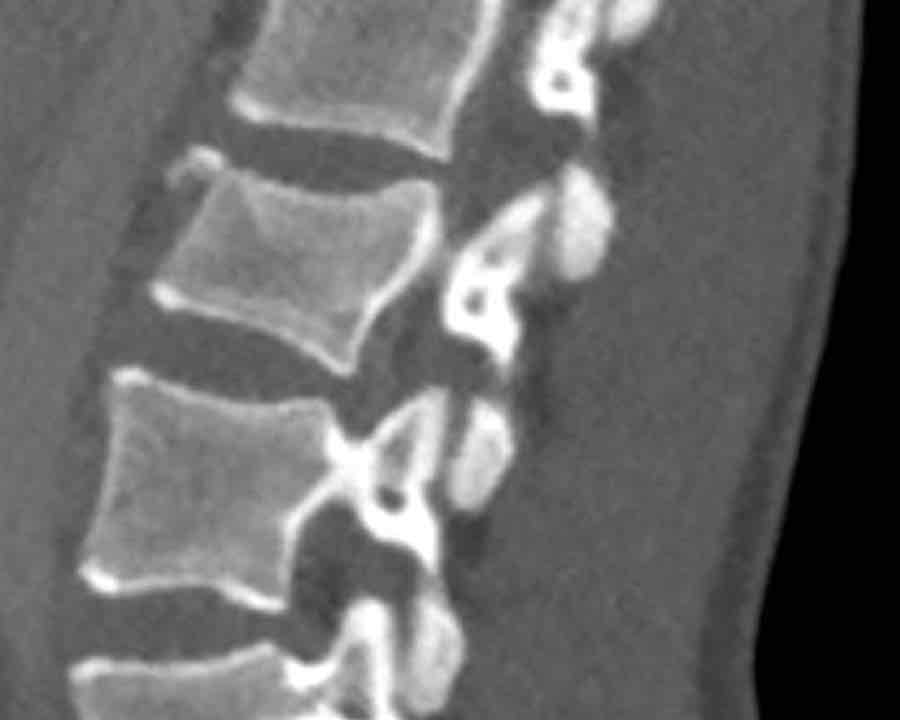

Findings:

- No C or B injury

- Fractures vertebral body with involvement of upper endplate (1 point) and posterior wall (2 points)

Conclusion

Injury type A3